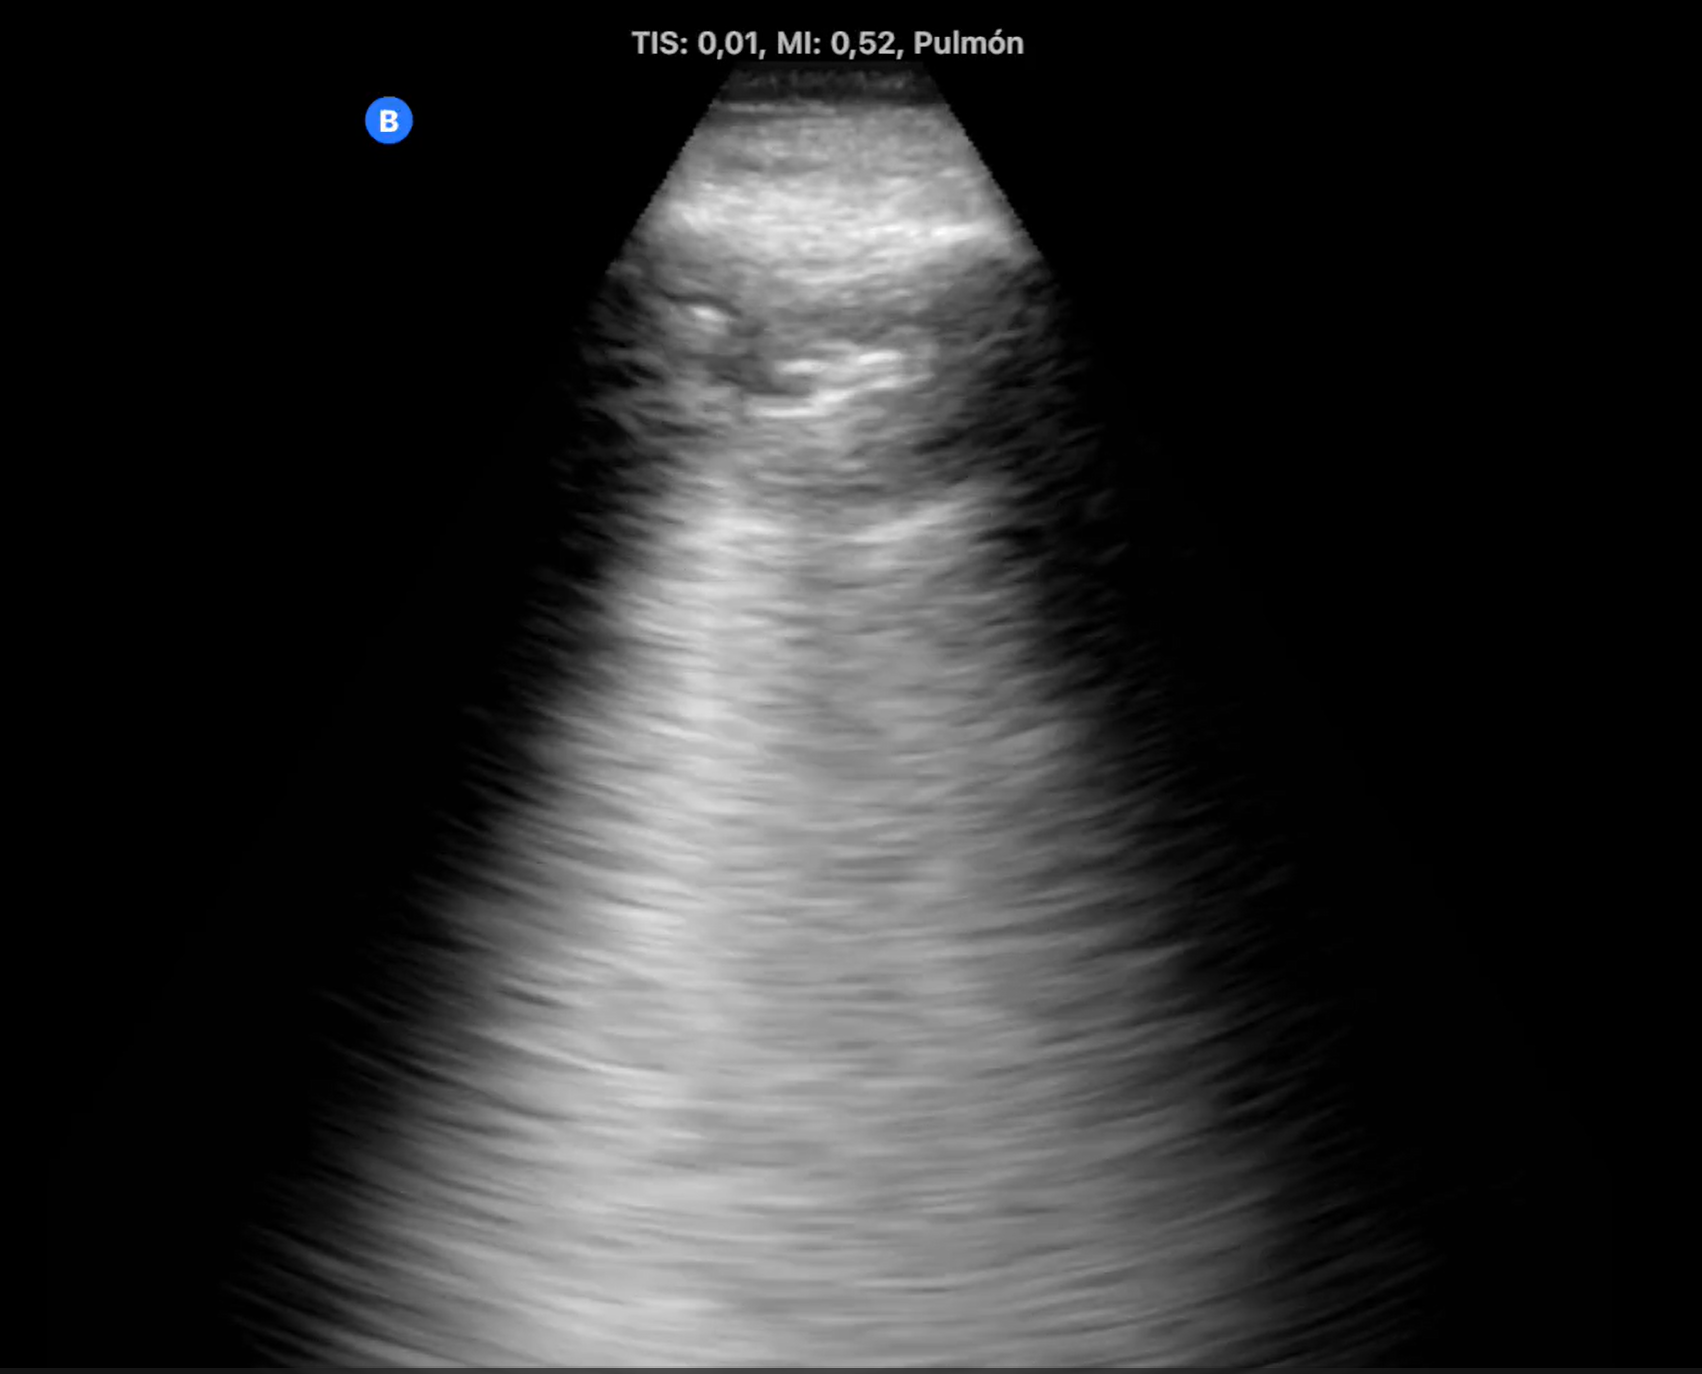

A través de una serie de casos clínicos surgidos tanto en la consulta como en los domicilios, hemos llevado a cabo una revisión de cómo aplicar la ecografía clínica para mejorar el diagnóstico diferencial del paciente con disnea y su posterior seguimiento. Tras la realización de dicha revisión bibliográfica nos reunimos los responsables de ecografía del centro de salud para realizar una serie de sesiones clínica y compartir nuestra experiencia y plantear un algoritmo sencillo de aplicar en nuestra práctica diaria.

La disnea es una sensación subjetiva de dificultad para respirar siendo común a múltiples situaciones clínicas de elevada prevalencia. Las causas más frecuentes, las de origen respiratorio y las de causa cardiaca, incluso comparten factores de riesgo, por lo que en ocasiones coinciden en el mismo paciente. En estas circunstancias no resulta sencillo solo por la clínica intuir cual puede ser el origen de la disnea. La ecografía multiórgano, constituye una herramienta muy útil para determinar o descartar el origen cardiaco de la disnea. Siendo imprescindible en los pacientes inmovilizados, en los que los ecógrafos ultraportables nos ha aportado un nuevo manejo de la disnea en el paciente domiciliario.

La ecografía multiórgano junto con la mejora de la portabilidad de los ecógrafos nos permiten hacer un diagnóstico más certero del paciente que consulta por disnea tanto en el centro de salud como en su domicilio.